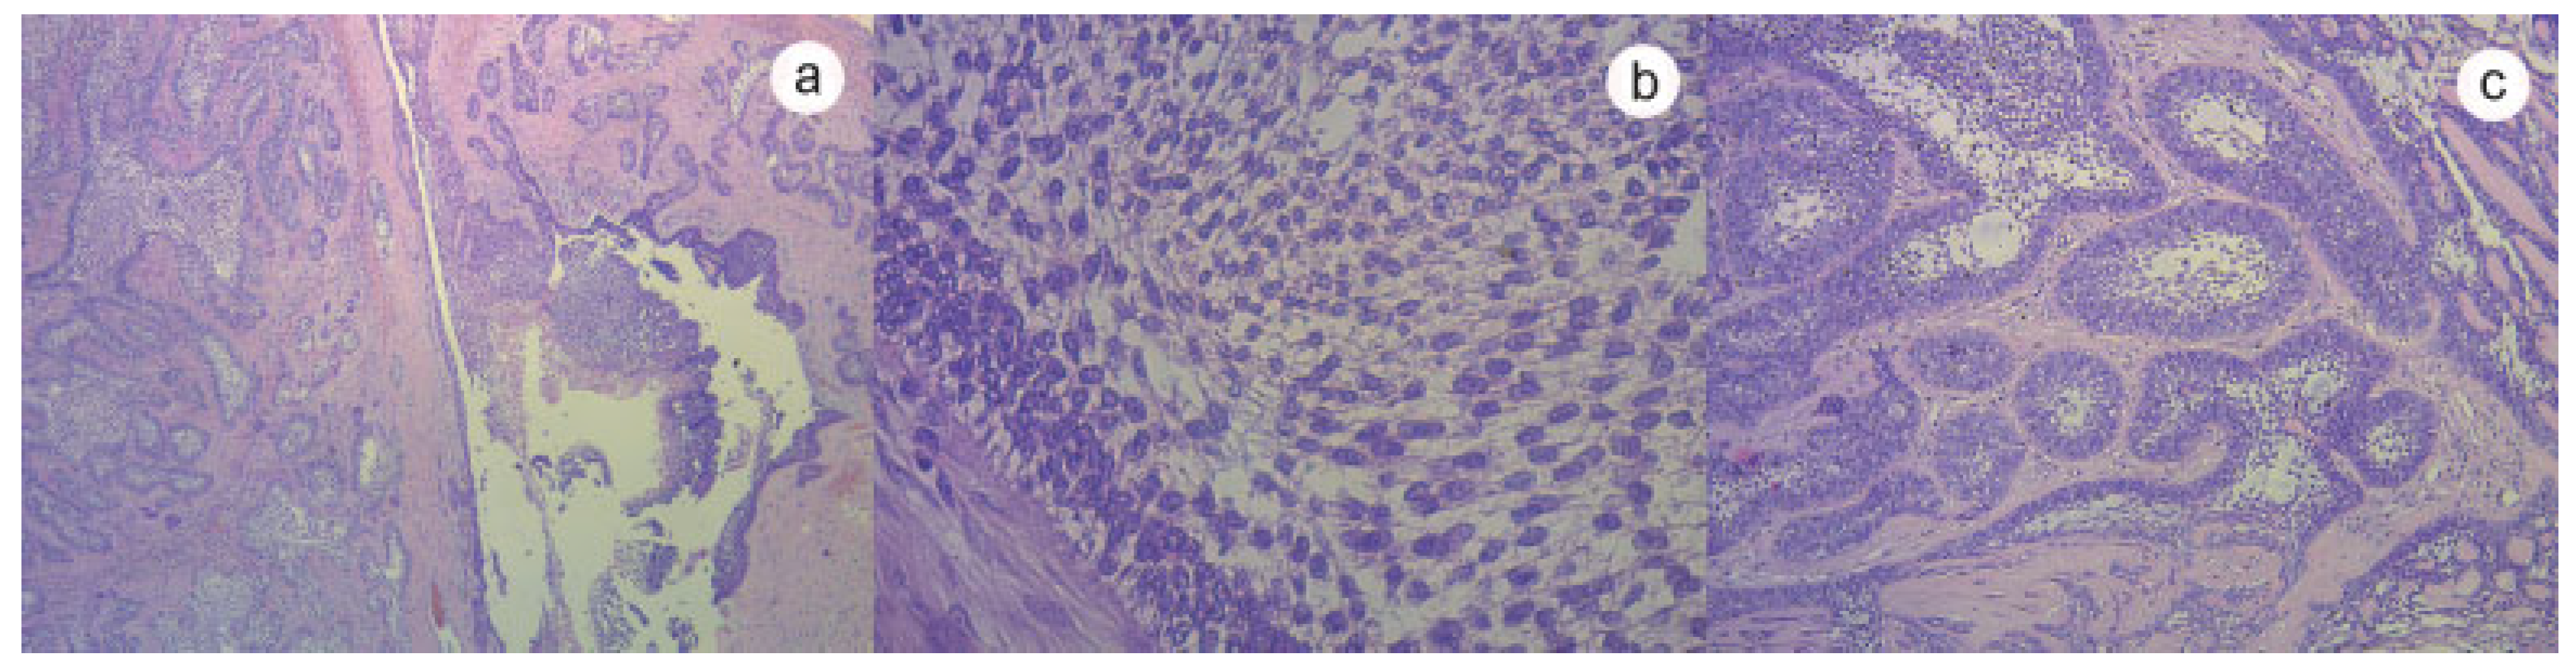

:Case History

Discussion